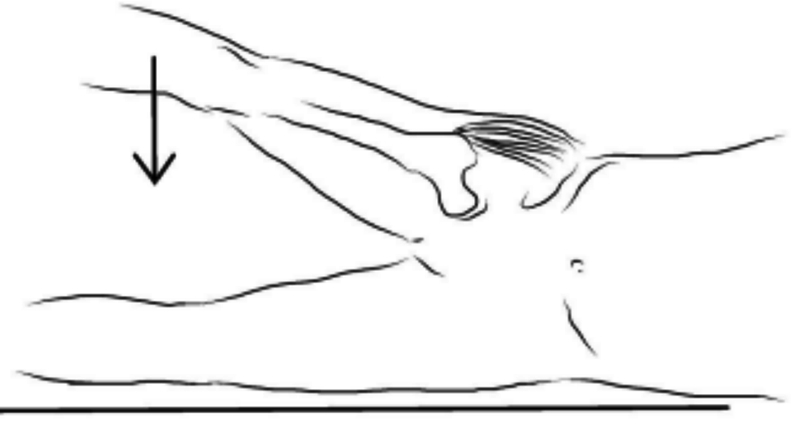

1. 术后脊髓漂移牵拉神经根,解剖学上C5神经根较短;

L5神经根定位的主要标志性表现之“足下垂”

Foot drop(足下垂):是指脚背抬高时足部无法向上抬起,导致足部处于下垂状态的情况。(足背屈肌无力)足下垂时因小腿前部肌群无力,足无法上抬,走路时病人被迫只能将患肢大幅度抬高,才能使患肢足完全离地。

1. 解剖学上L5神经根移行区域长;致压因素复杂;